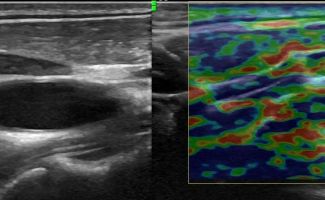

Η Ελαστογραφία αποτελεί ένα εξαιρετικά χρήσιμο εργαλείο στο Υπερηχογράφημα Λεμφαδένων Τραχήλου. Με την Ελαστογραφία, μπορούμε να αξιολογήσουμε την ελαστικότητα των λεμφαδένων, βοηθώντας έτσι στη διάκριση μεταξύ καλοήθων και διηθημένων λεμφαδένων. Αυτό είναι ιδιαίτερα σημαντικό στη διαδικασία της διάγνωσης.